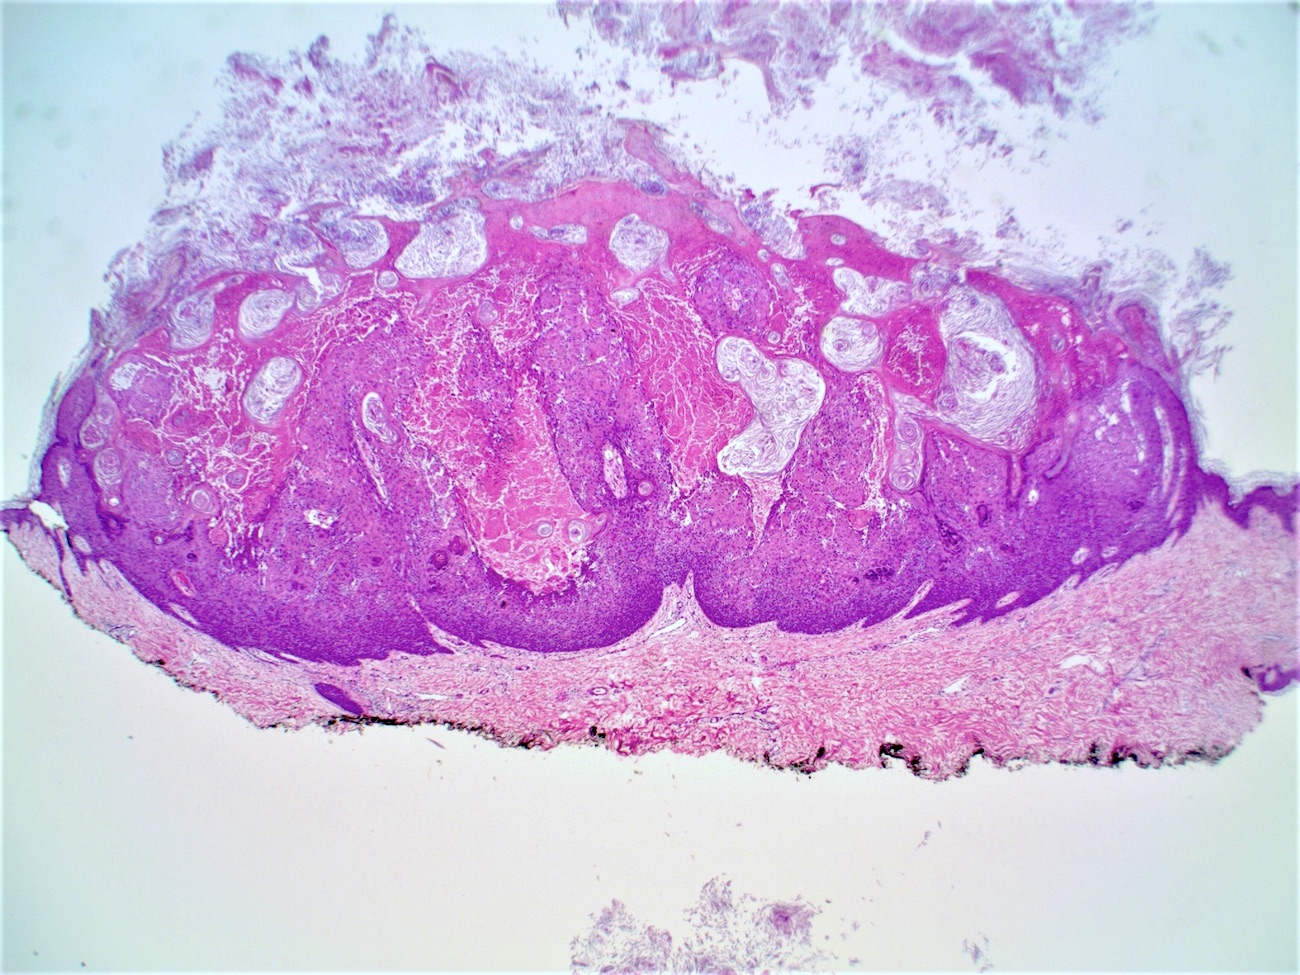

Microscopic (histologic) description

- Well circumscribed, endophytic tumor with large lobules or finger-like extensions that resemble expanded follicles

- Variable number of squamous eddies

- Occasional mitoses within peripheral basaloid cells

- Histologic variants have been described (J Cutan Pathol 1984;11:387):

- Papillomatous wart-like: exophytic with overlying hyperkeratosis and parakeratosis

- Keratoacanthoma-like: central exoendophytic mass

- Cystic type: irregular clefts within tumor and formation of small cysts

Microscopic (histologic) images